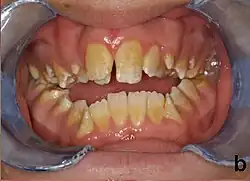

People with amelogenesis imperfecta may have teeth with abnormal color: yellow, brown or grey; this disorder can affect any number of teeth of both dentitions. Enamel hypoplasia manifests in a variety of ways depending on the type of AI an individual has (see below), with pitting and plane-form defects common.[4] The teeth have a higher risk for dental cavities and are hypersensitive to temperature changes as well as rapid attrition, excessive calculus deposition, and gingival hyperplasia.[5] The earliest known case of AI is in an extinct hominid species called Paranthropus robustus, with over a third of individuals displaying this condition.[6]

AI can be classified according to their clinical appearances:[19]

- Type 1 - Hypoplastic

- Enamel of abnormal thickness due to malfunction in enamel matrix formation. Enamel is very thin but hard & translucent, and may have random pits & grooves. Condition is of autosomal dominant, autosomal recessive, or x-linked pattern. Enamel differs in appearance from dentine radiographically as normal functional enamel.[20]